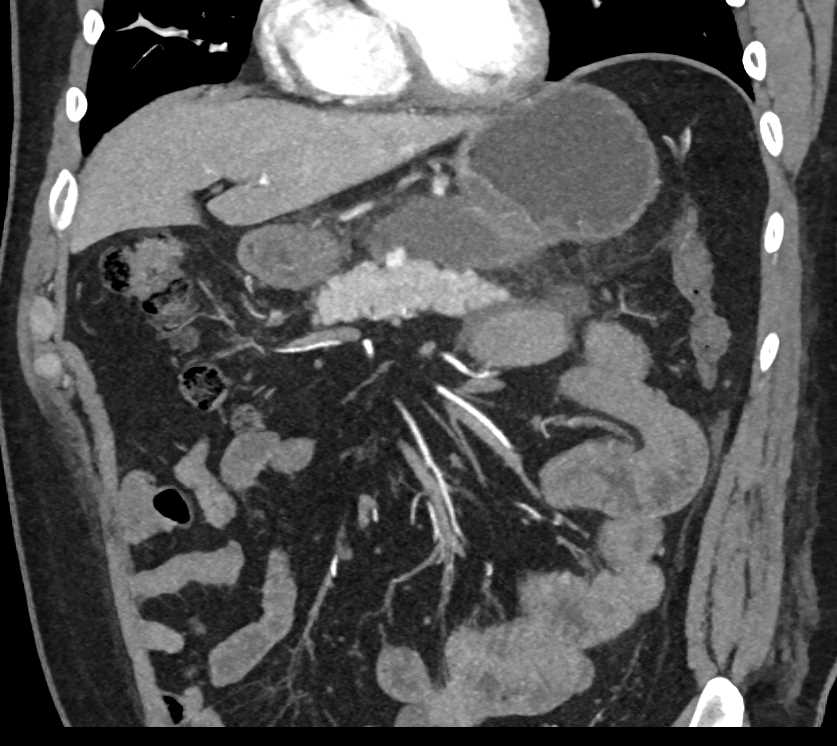

Gastric Adenocarcinoma in the Body of the Stomach